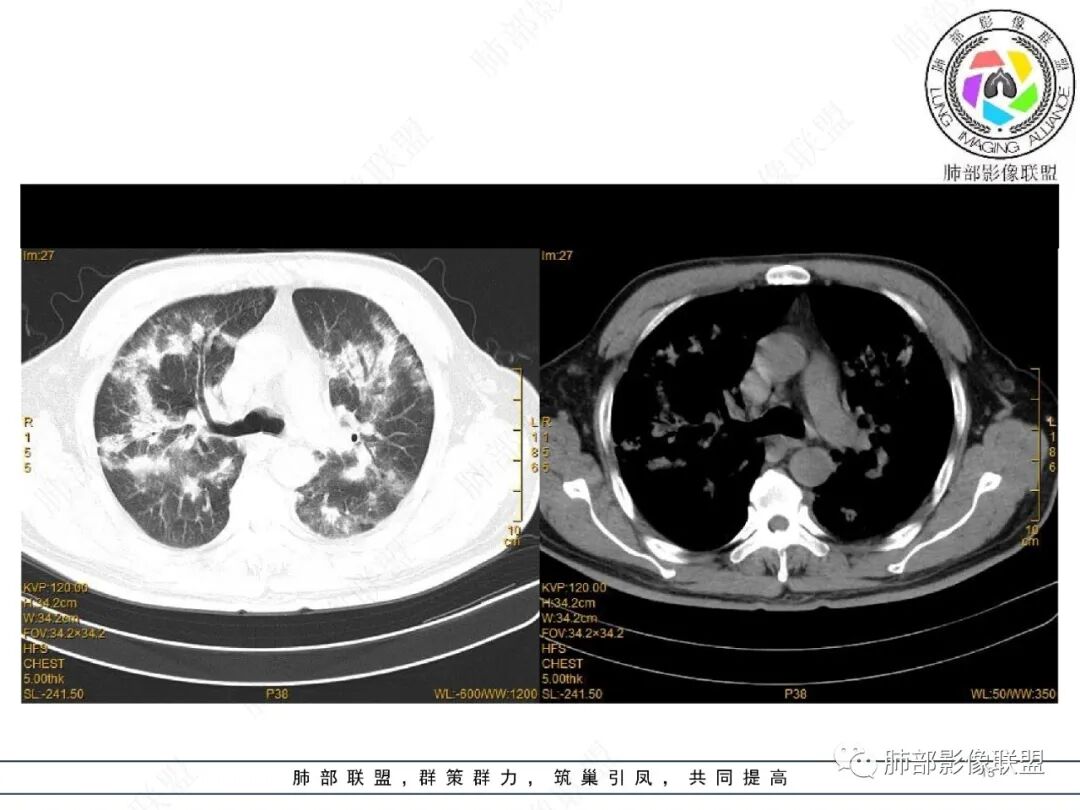

2022.2.17CT显示两肺中内带多发结节影、斑片影、条索影,部分病灶侧向融合与胸膜平行。部分病灶沿着支气管血管束分布、其内支气管稍扩张。部分病灶呈反晕征。大部分病灶边界显示清晰,部分病灶周围可见边界不清的GGO。2022.4.12CT显示两肺中内带多发结节影、条索状、条带状高密度影,边界收缩平直凹陷,大部分病灶沿着支气管血管束分布,亦有位于胸膜下侧向融合与胸膜平行的病灶。总体与第一次CT对比两肺病灶明显吸收。